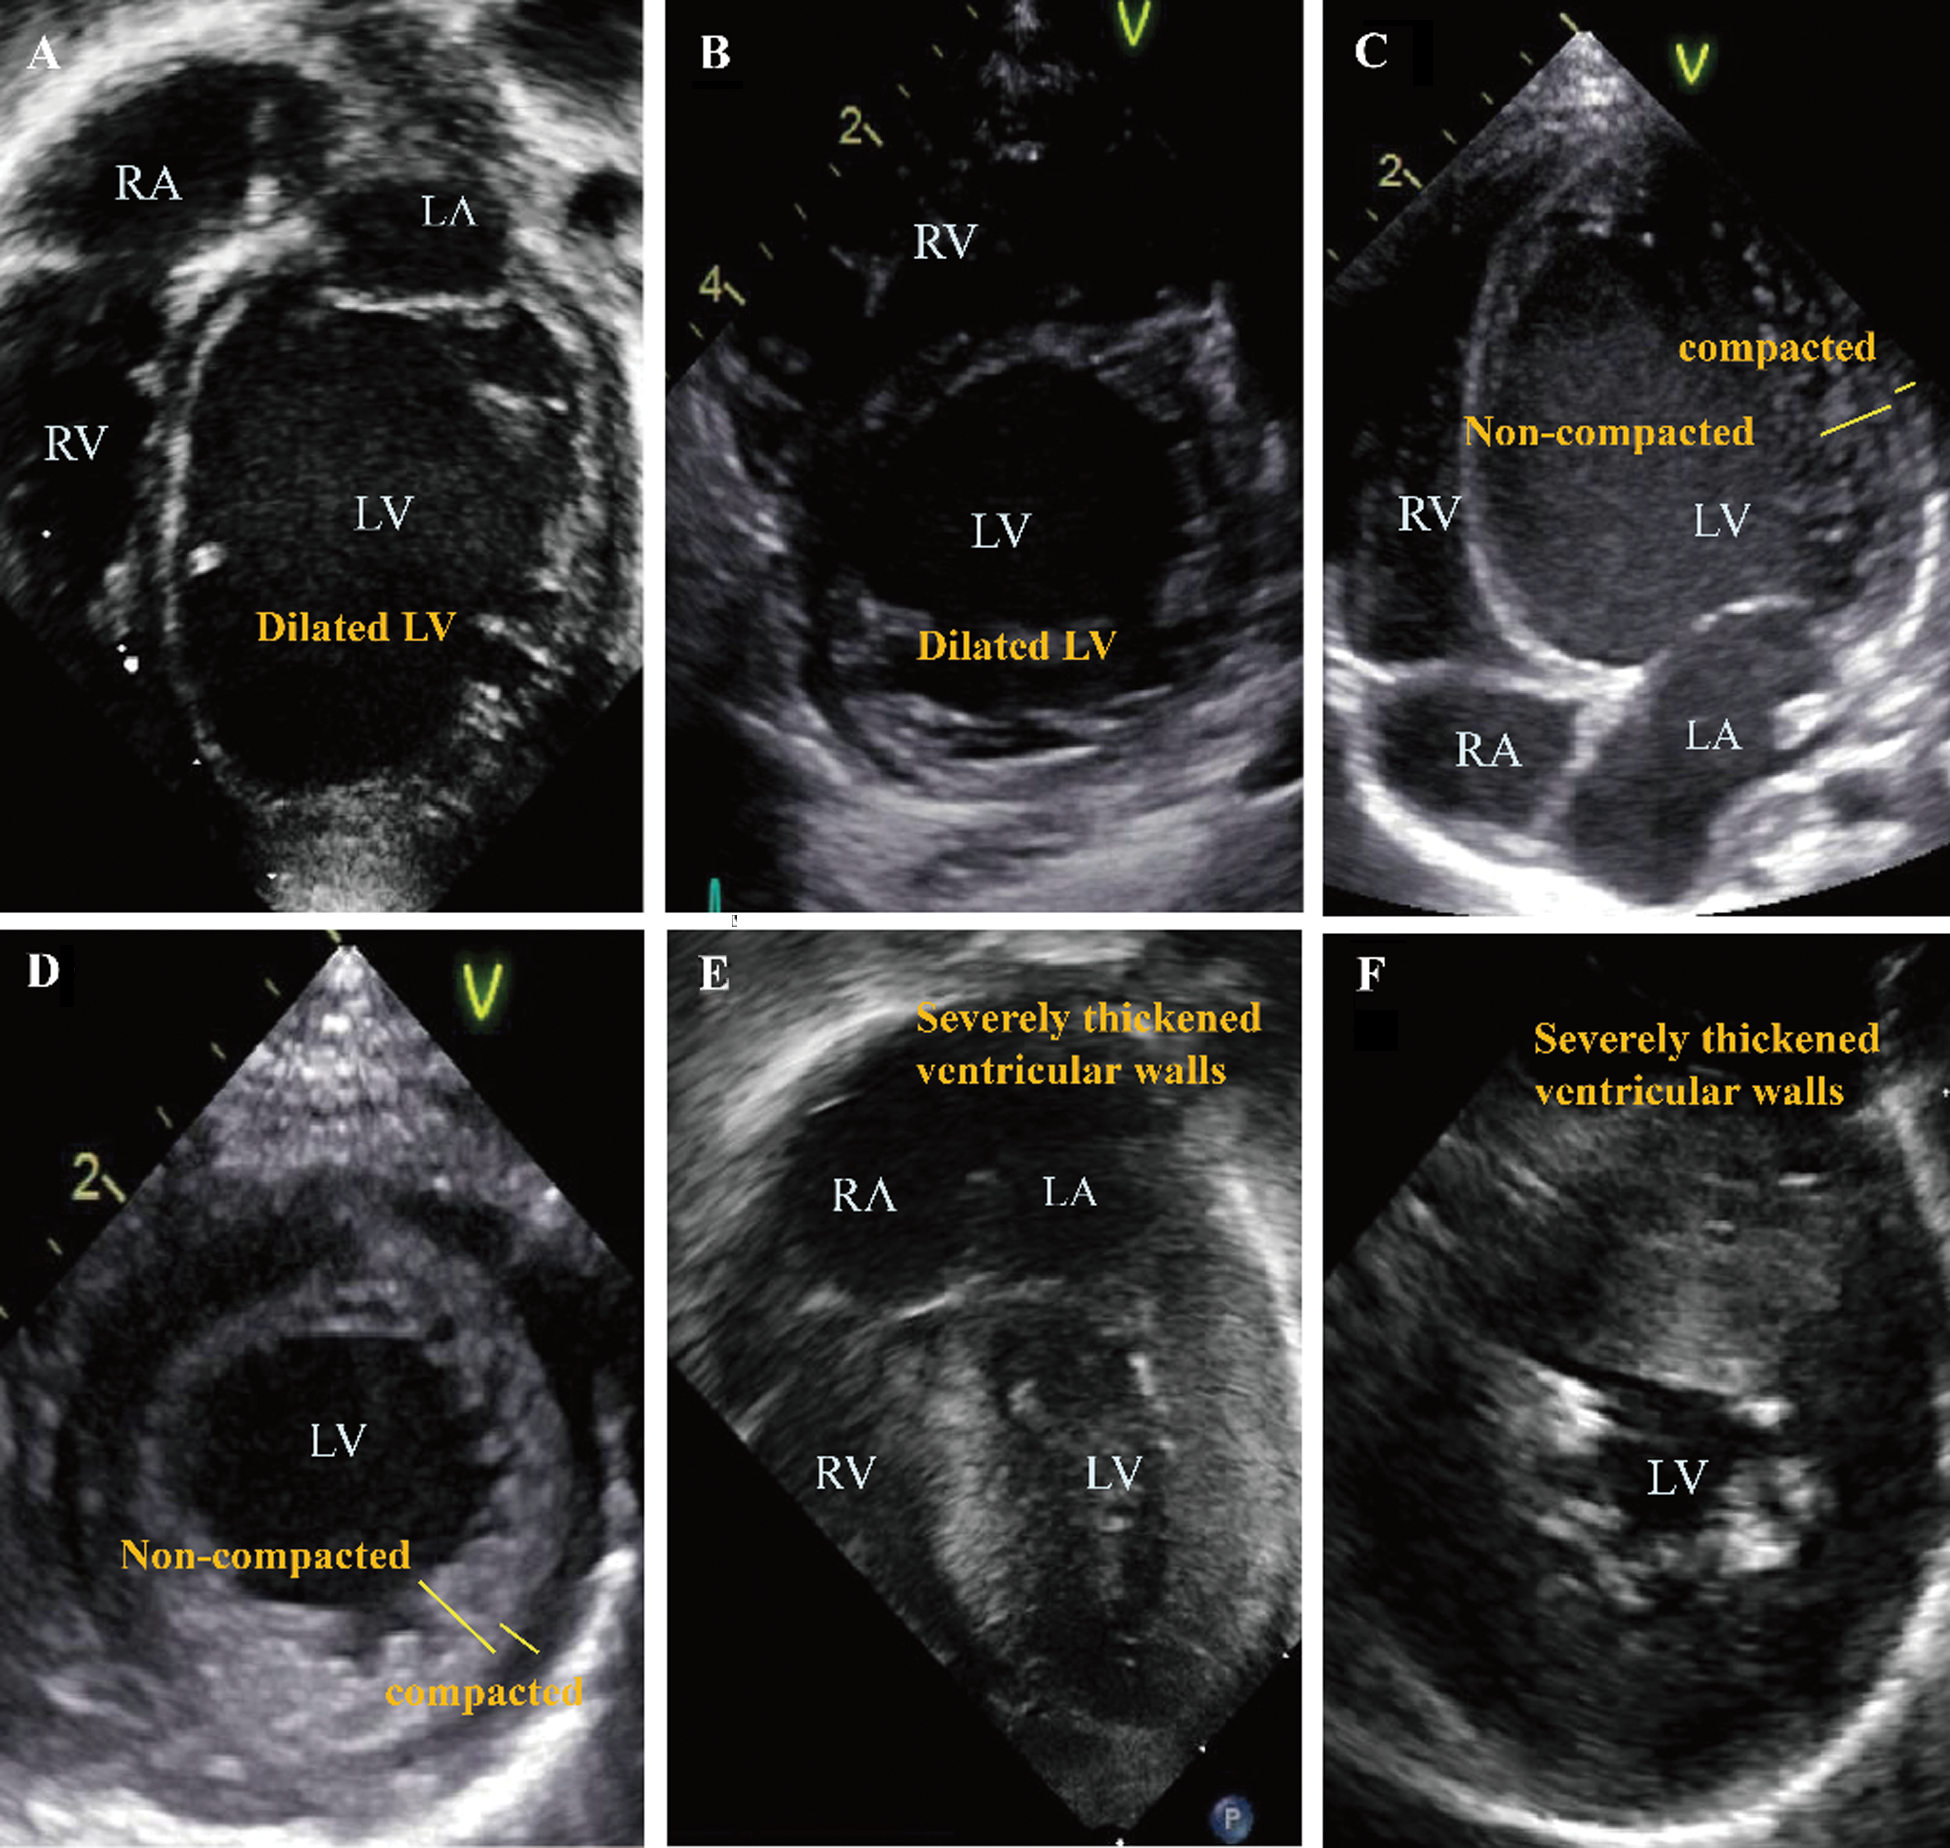

The echocardiography images representing each phenotype are summarized in Fig. 1. Patient No. 1 with DCMP shows dilated left ventricle (Figs. 1A, 1B), Patient No. 4 with LVNC shows non-compacted excessive trabeculation (Figs. 1C, 1D), Patient No. 7 with HCMP shows severe thickening of the ventricular wall (Figs. 1E, 1F). The electrocardiogram representing each phenotype is shown in Fig. 2. Left ventricular hypertrophy was observed in patient No. 1 with DCMP and patient No. 4 with LVNC (Figs. 2A, 2B), and biventricular hypertrophy and wall strain pattern were observed in patient No. 7 with HCMP (Fig. 2C).

Figure 1: Echocardiographic 4-chamber and parasternal short axis images for different phenotypes. (A, B) An infant with a dilated cardiomyopathy (patient No. 1), (C, D) A neonate with a left ventricular non-compaction cardiomyopathy (patient No. 4), (E, F) A neonate with a hypertrophic cardiomyopathy (patient No. 7). Abbreviations: RA, right atrium; LA, left atrium; RV, right ventricle; LV, left ventricle